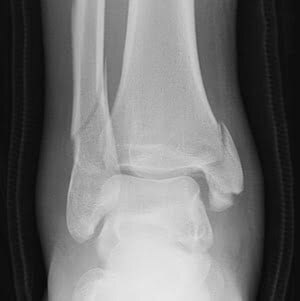

H άρθρωση της ποδοκνημικής αποτελείται από 3 οστά: την κνήμη, την περόνη και τον αστράγαλο. Τα οστά αυτά συγκρατούνται μεταξύ τους με μια σειρά από ισχυρούς συνδέσμους, με σημαντικότερους την «συνδέσμωση» και τον δελτοειδή σύνδεσμο. Το κάτω πέρας της κνήμης και της περόνης ονομάζονται έσω και έξω σφυρό, αντίστοιχα. Το οπίσθιο τμήμα του κάτω πέρατος της κνήμης ονομάζεται οπίσθιο σφυρό. Αυτές είναι και οι δομές που υφίστανται συνηθέστερα κατάγματα. Τα κατάγματα αυτά μπορεί να είναι μεμονωμένα, πχ μεμονωμένο κάταγμα έσω σφυρού, ή κάταγμα έξω σφυρού, ή σύνθετα, πχ αμφισφύριο κάταγμα ή τρισφύριο κάταγμα. Μπορεί επίσης να συνοδεύονται από τραυματισμούς των συνδέσμων.

Η θεραπεία των καταγμάτων της ποδοκνημικής άρθρωσης ποικίλει ανάλογα με το είδος και τη σταθερότητα του κατάγματος. Μεμονωμένα ή ελάχιστα παρεκτοπισμένα κατάγματα είναι συνήθως σταθερά και μπορούν να αντιμετωπιστούν με έναν νάρθηκα ή με μία μπότα βάδισης για μερικές εβδομάδες. Σύνθετα κατάγματα (αμφισφύρια ή τρισφύρια), ή κατάγματα με συνοδό συνδεσμική βλάβη, είναι συχνά ασταθή και μπορεί να χρειαστούν χειρουργείο.